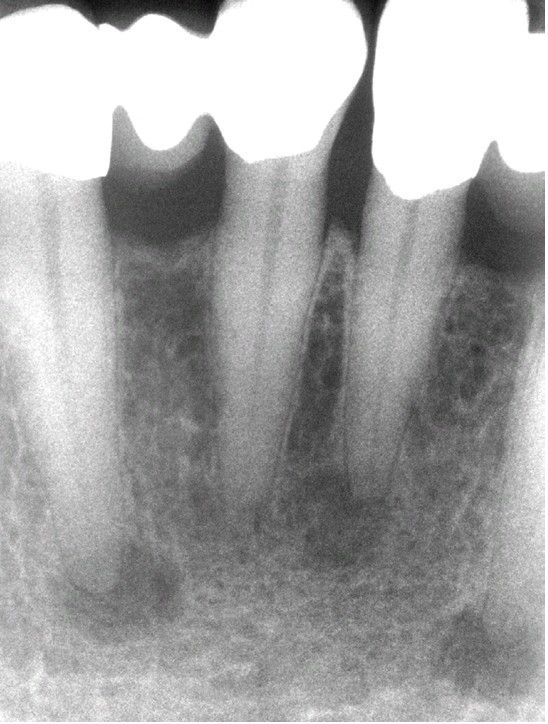

Periapical Cemento-Osseous Dysplasia.

Periapical radiograph showing multiple radiolucent lesions at the apices of the anterior mandibular teeth